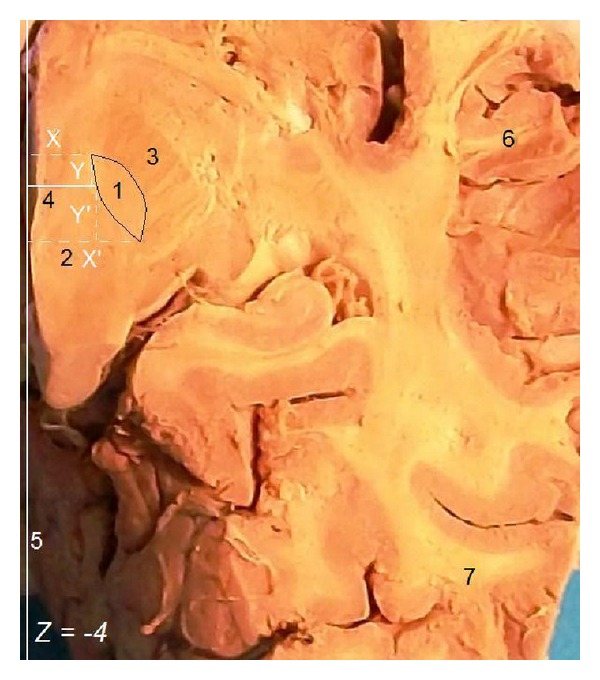

目的。我们的目的是提供一项以临床为导向的联合研究,重点研究人类STN的详细解剖结构,并在很大程度上考虑其靶向性。方法。在我们的成像研究中,我们使用了来自26名神经外科患者的脑磁共振图像(mri),并在我们的解剖研究中使用了来自18名尸体捐赠者的正常大脑的32个大脑半球。我们测量并分析了STN的尺寸(基于其立体定向坐标)。结果。在立体定向水平Z = -4时,mri上STN长度为7.7 mm,解剖标本上为8.1 mm。核磁共振成像宽度为6mm,解剖标本宽度为6.3 mm。MRI横切片平均可见STN 3.2片,最大尺寸为8.5 mm。mri上关节间距离26.3 mm,解剖标本上关节间距离27.3 mm。个体间STN的宽度和长度差异有统计学意义

Purpose. Our purpose was to provide a combined clinically oriented study focused on the detailed anatomy of the human STN, with great respect to its targeting. Methods. For our imaging study, we used cerebral magnetic resonance images (MRIs) from 26 neurosurgical patients and for our anatomic study 32 cerebral hemispheres from 18 normal brains from cadaver donors. We measured and analyzed the STN dimensions (based on its stereotactic coordinates). Results. At stereotactic level Z = -4, the STN length was 7.7 mm on MRIs and 8.1 mm in anatomic specimens. Its width was 6 mm on MRIs and 6.3 mm in anatomic specimens. The STN was averagely visible in 3.2 transverse MRI slices and its maximum dimension was 8.5 mm. The intercommissural distance was 26.3 mm on MRIs and 27.3 mm in anatomic specimens. We found statistically significant difference of the STN width and length between individuals <60 and ≥60 years old. Conclusion. The identification of the STN limits was easier in anatomic specimens than on MRIs and easier on T2 compared to T1-weighted MRIs sections. STN dimensions appear slightly smaller on MRIs. Younger people have wider and longer STN.